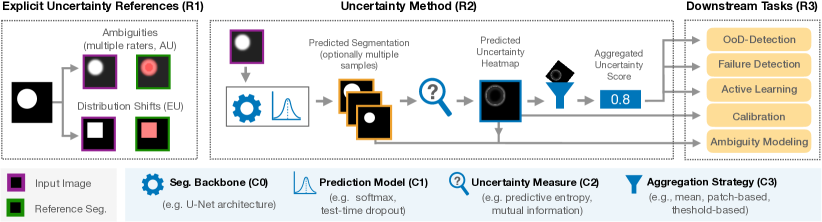

This work bridges the gap between theoretical advancements in uncertainty estimation and its real-world application in segmentation systems by presenting a framework for standardized and systematic validation (see Figure 1). The framework features 1) a controlled environment for studying data ambiguities as well as distribution shifts, 2) systematic ablations of relevant method components, and 3) test-beds for the five predominant uncertainty applications: Out-of-Distribution-detection (OoD-D), active learning (AL), failure detection (FD), calibration (CALIB), and ambiguity modeling (AM). We demonstrate the effectiveness of our proposed framework based on an exemplary empirical study that sheds light on the unanswered questions and current inconsistencies in the field and allows us to compile a list of hands-on recommendations.

To effectively discuss pitfalls and challenges in the field of uncertainty estimation for segmentation, we begin by establishing a common language by defining components of an uncertainty method.

C0 - Segmentation Backbone. The segmentation backbone is the fundamental building block for uncertainty estimation, depicting the method’s architecture, e.g., a U-Net architecture (Ronneberger et al. (2015)). As well-established architectures exist, C0 is often fixed in uncertainty studies.

C1 - Prediction Model. The prediction model (PM) operates based on the segmentation backbone and produces the final predicted class scores for segmentation. Depending on the PM, a single set (”deterministic”) or multiple sets (”sampling-based”) of scores per input image can be generated. The PM may include dedicated training and inference paradigms, like ensemble training or test-time dropout (TTD). Examples of PMs include deterministic models like softmax, Bayesian approaches, and probabilistic models like stochastic segmentation networks (SSNs) (Monteiro et al. (2020)).

C2 - Uncertainty Measure. The uncertainty measure involves computing an uncertainty score per pixel based on predicted class scores, which can be represented as an uncertainty heatmap. Examples of uncertainty measures include expected entropy and mutual information.

C3 - Aggregation Strategy. The aggregation strategy is a unique component of uncertainty estimation for semantic segmentation that is not needed in tasks such as image classification. Here, the pixel-level uncertainty heatmap is aggregated to a single scalar value at the desired level of granularity depending on the downstream task (e.g., patch-level or image-level). A simple example of an aggregation strategy is to compute the sum or mean over the pixel-level uncertainties.